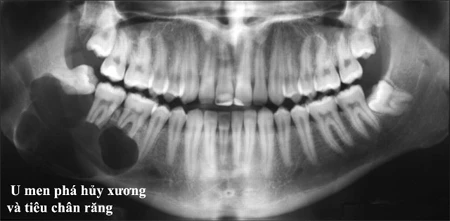

X-quang không cho hình ảnh đặc hiệu, thường là hình đa nang cho phép ta nghĩ tới u men:

+ Có nhiều đám tròn hay Oval, kích thước không bằng nhau, đồng dạng, ít cản quang, bờ mảnh và đều, tựa vào nhau và chồng lên nhau cho ta hình ảnh “bong bóng xà phòng”. Vỏ xương hàm bị mỏng dần, có chỗ bị u đẩy phồng lên.

+ Nhưng hay gặp là hình thấu quang rộng, giới hạn bằng nhiều đường viền ở xung quanh, có các vách xương mảnh ngăn cách ở giữa tạo thành nhiều xoang.

+ Ở giai đoạn muộn, u men cho hình ảnh một buồng thấu quang lớn, bờ nham nhở, u làm vỏ xương mỏng đi dần và phồng lên. Ở hàm dưới nó có thể đẩy phồng hõm Sigma nhưng lồi cầu vẫn giữ được hình dạng.

* Thường gặp hình ảnh tiêu chân răng do u phát triển chậm.